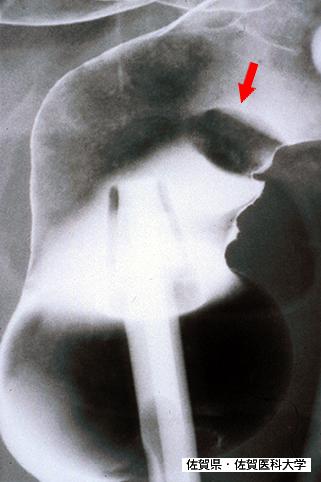

Leucemia a células T del Adulto (ATL) que evidenció múltiples lesiones en estómago y Colon (caso presentado por el Dr. Mizuguchi de la Universidad Médica de Saga)

Tumor Sanguíneo - Linfático Maligno/ATL(Leucemia a células T adultas)

parte(separada por órganos)

método de exámen

Rayos X

10 - 14

múltiples tumores(en un mismo órgano)

presente(simultáneo)

múltiples tumores(en varios órganos)